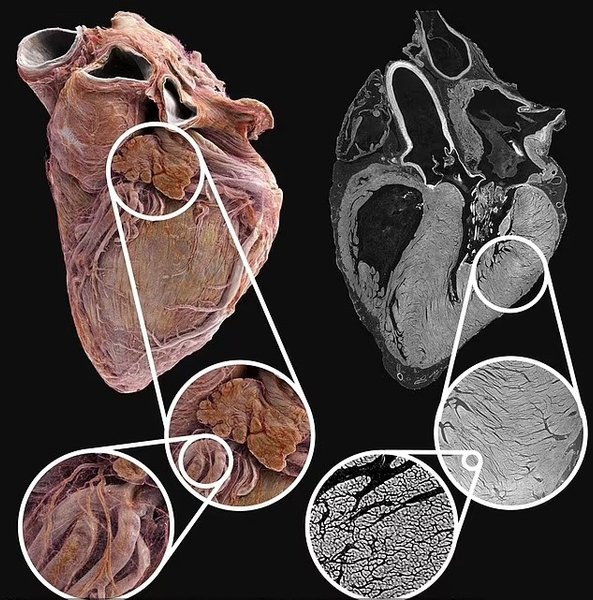

Ученые заглянули в самое сердце человека | Фото: University College London

В результате ученым удалось заглянуть в самое сердце человека и изучить его анатомическую структуру в мельчайших деталях, чего не удавалось никогда прежде. По словам исследователей, им, по сути, удалось запечатлеть анатомическую структуру сердца размером до 20 микрометров, что соответствует половине ширины человеческого волоса.

В некоторых областях визуализация была выполнена на клеточном уровне — в результате ученые смогли показать отдельные клетки человеческого органа. Видео было снято экспертами из Университетского колледжа Лондона и Европейской установки синхротронного излучения во Франции.

По словам соавтора исследования, профессора Питера Ли, фактическим им с коллегами удалось создать "атлас человеческого сердца". Визуализация позволяет рассмотреть орган в глобальном масштабе, а также увеличить изображение, чтобы рассмотреть отдельные сердечно-сосудистые особенности в беспрецедентных деталях.

Здоровое сердце: методика команды фиксирует анатомическую структуру сердца на расстоянии до 20 микрометров

Для визуализации использовали два сердца умерших доноров: здоровое сердце принадлежало 63-летнему белому мужчине без каких-либо проблем с сердцем; второе сердце принадлежало 87-летней белой женщине с историей ишемической болезни сердца — орган был ослаблен из-за снижения кровотока.

В своей работе ученые использовали рентгеновский метод, известный как иерархическая фазово-контрастная томография (HiP-CT). В результате им удалось получить изображения сердца в масштабе 20 микрометров. По словам профессора Ли, одним из основных преимуществ этого метода является то, что он позволяет получить полное трехмерное изображение органа, которое примерно в 25 раз лучше, чем клинический компьютерный томограф.